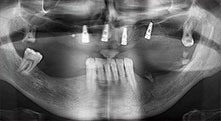

Professor Dr. Dr. Emanuel Bratu, maxillofacial surgeon, oral surgeon and prostheticist, is head of the implantology departments at two Romanian universities. He runs a renowned private hospital in Timisoara and is an internationally known researcher. In the interview Bratu explains why he considers that the W&H Piezomed piezosurgical device, and particularly two patented saws, have become essential for bone surgery.

Bratu: We routinely use the instruments for harvesting bone blocks and splitting alveolar ridges. We also use the Piezomed B6/B7 for osteotomy of impacted teeth and removing failed implants. All indications that require deep, clean cuts.

Bratu: We prefer to harvest bone from the external oblique ridge of the posterior mandible, not from the interforaminal region. After the soft-tissue incision, we use the new saws to define the amount of bone to harvest. With this approach, we also use them for the entire preparation in almost 80% of cases. We may also use other piezo instruments and then at the end a chisel to mobilize the block. We find that this is a very effective surgical technique.